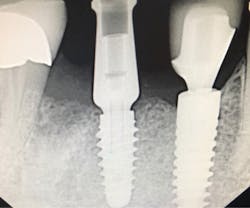

DURING the last few years, some of the greatest innovations in implant designs have occurred in relation to the immediate placement of implants. “Old-school” implant designs generally involved cylindrical, nontapered implant bodies with relatively dull and shallow threads. But modern, more recent implant designs have included tapered implant bodies with sharper, deeper, and more aggressive threads. This has allowed for more engagement in the bone (osseocompatibility), with greater primary stability, which has equated to earlier loading times. These more modern designs have also created greater success rates, which has led to the immediate implant procedure being more popular with general practitioners in the United States.

Another reason immediate placement is advantageous is that once the extraction is complete, the hole is usually already in the proper place for the implant. You may have to redirect your osteotomy slightly palatally, mesially, or distally, but the socket serves as an excellent guide for placement. In some cases, especially premolars, you can use an implant with aggressive threads to place without any osteotomy at all. You can engage the mesial and distal walls to achieve primary stability. This greatly shortens the appointment time, lowers risk, and increases patient satisfaction. Figures 1 and 2 show a MorsTorq in site No. 21 that was placed after an atraumatic extraction during my most recent two-day Louisiana Implant Institute course. Note the sharp threading on the MorsTorq, which allows for optimized immediate placement performance.There are some circumstances where immediate placement is not desirable. If the socket is too large to engage the mesial and distal walls and vital anatomical structures are located just apical to the socket, immediate placement is not recommended. Chronically infected sites also present a higher risk for immediate placement. If you can completely rid the socket of all soft tissue and the patient has the appropriate antibiotics onboard, it is possible. However, most of these cases are more predictably treated with early placement (waiting four to six weeks without grafting) or delayed placement (three to six months with grafting).

When placing an immediate implant, you must maintain a gap of at least 2 mm between the implant and buccal wall to prevent resorption of the plate and thread exposure.Next in the series